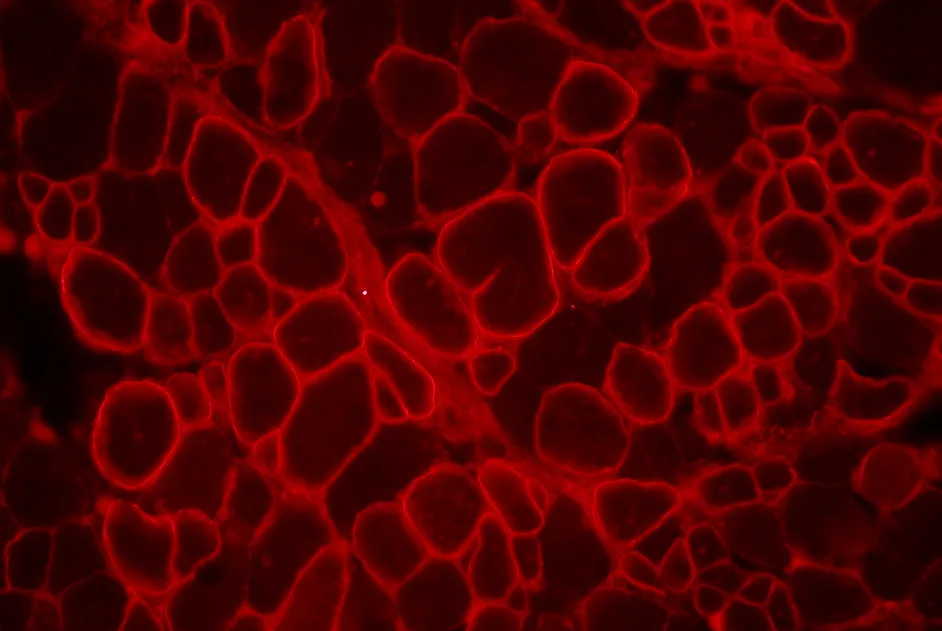

Une équipe franco-américaine a utilisé les TALEN pour restaurer le cadre de lecture dans l’exon 51 du gène de la dystrophine. L’expression de la dystrophine a été restaurée dans les myoblastes et fibroblastes de la peau transfectés en culture.

Une équipe franco-britannique, en collaboration avec la société Cellectis, a corrigé, dans des myoblastes, le gène de la dystrophine ayant perdu les exons 45 à 52 avec des méganucléases. L’expression de la dystrophine complète (incluant les exons 45 à 52) a ainsi été observée dans les myoblastes transfectés.

Ces résultats apportent la preuve de principe de l’efficacité d’une stratégie de chirurgie du gène pour restaurer l’expression de la dystrophine en ciblant différentes parties du gène.